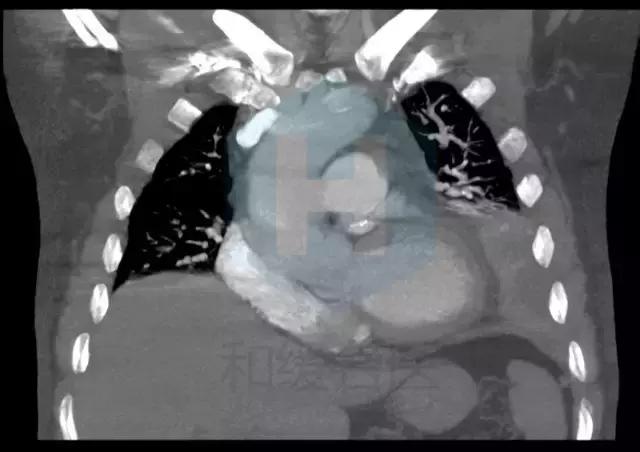

从CT来看,是比较典型的肺栓塞的表现,应该做肺动脉造影检查。

患者有胸痛,胸闷,1型呼吸衰竭,胸部影像示左下肺为“三角形”肺实变影伴胸腔积液,高度怀疑存在肺栓塞,建议行CTPA检查和肺核素通气/灌注现象检查。同时需排除肺栓塞原因,如肿瘤,自身免疫性疾病等。肺栓塞也会有黄疸和溶血表现。 胸痛特点和表现不符合心绞痛,左侧胸腔积液与左侧肺部病变有关。 患者黄疸考虑为溶血性黄疸,应行查找溶血原因,此外,血红蛋白有下降,便潜血阳性,有同时伴有失血可能,建议查血网织红细胞计数评价贫血情况,应行胃肠镜检查以明确消化道出血原因。 目前低价血症原因考虑不除外副肿瘤综合症可能,注意纠正电解质紊乱。 可视医院条件,建议安排下一步检查:胸部增强CT及CTPA,或肺通气/灌注检查,下肢及深静脉超声,血肿瘤标志物,血网织红细胞计数,自身免疫抗体(ANA,ENA,ANCA)等,胃肠镜检查。 由于目前有消化道出血风险,暂不建议抗凝治疗。密切观察。